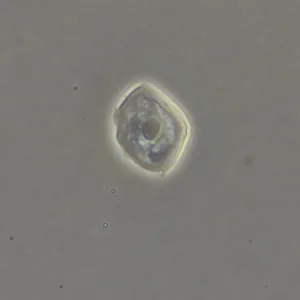

Фазово-контрастная микроскопия позволяет увидеть детали прозрачных образцов, которые практически не видны в светлом поле, и при этом не повреждать их окрашиванием. Метод применяют в разных сферах: медицине, биологии, ветеринарии, сельском хозяйстве, фармацевтике, экологии.

Оптика фазового объектива конструктивно дополнена фазовым кольцом в плоскости выходного зрачка. Фазовый объектив может работать и в фазовом контрасте, и в светлом поле, но в светлом поле демонстрирует не столь высокие результаты.